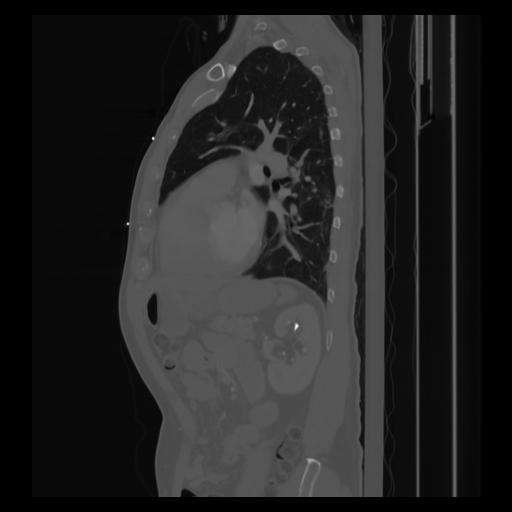

30 CUERPO,CE,Sagittal,3.000,CUERPO,Sagittal,